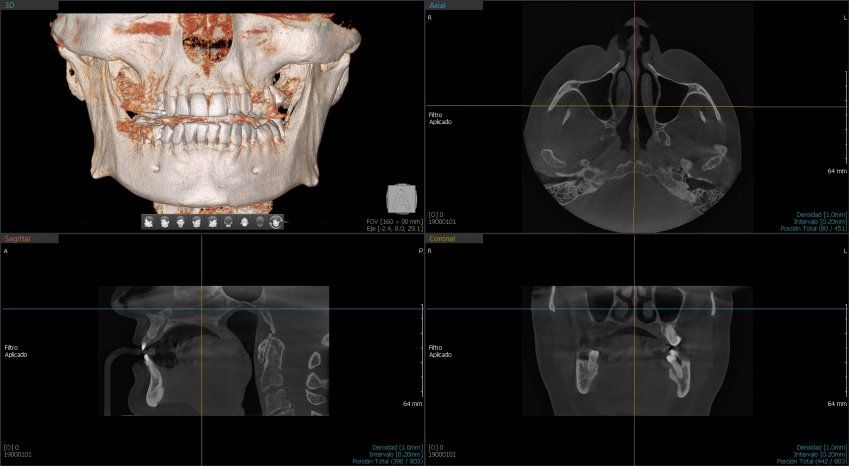

Green 16/18 ofrece una gama de campos de visión seleccionables. Multi FOV permite al usuario seleccionar el modo FOV óptimo y minimizar la exposición a áreas que no son la región de interés. Seleccione el tamaño adecuado de FOV entre 16×9/18×10, 12×9/13×10, 8×9 y 5×5 basado en una particular necesidad de diagnóstico. Cubre la región del arco completo, seno y la ATM izquierda / derecha y es adecuado para la mayoría de los casos de cirugía oral así como la cirugía de implantes múltiples. También puede medir el volumen de la vía aérea.